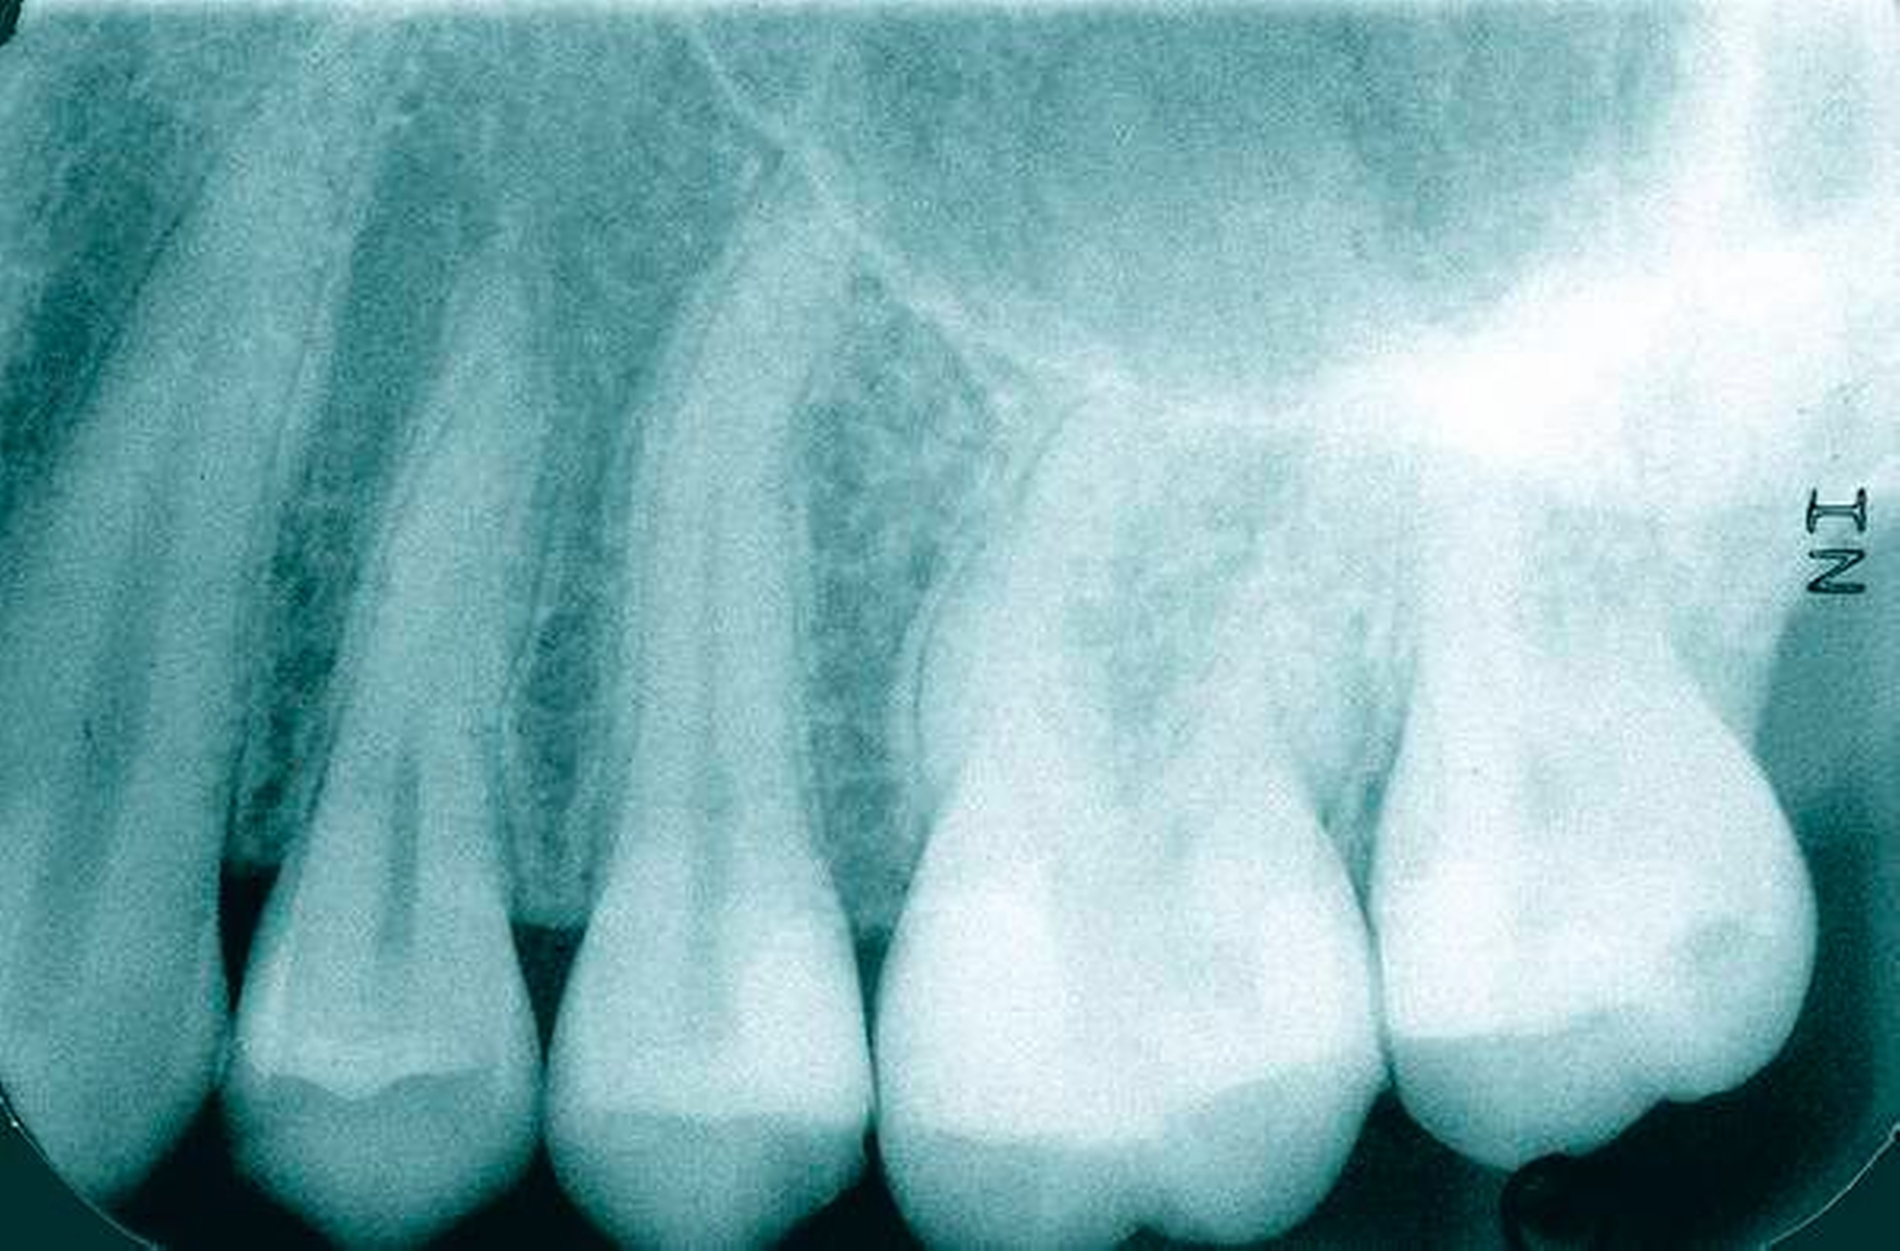

Im Gegensatz zu Reaktionsdentin wird Reparaturdentin definiert als Tertiärdentin, dessen Matrix nach dem Untergang der primären postmitotischen Odontoblasten als Reaktion auf einen Reiz hin gebildet wird [59, 90, 91]. Die Bildung von Reparaturdentin ist dabei unter biologischen Gesichtspunkten sehr viel komplexer als die von Reaktionsdentin, da in Fällen einer ausgeprägteren Verletzung der Pulpa, zum Beispiel nach mechanischer Pulpafreilegung, der primäre Odontoblast zerstört wird. Wie bereits ausgeführt, ist aber ohne Odontoblasten eine physiologische Dentinbildung nicht möglich. Trotzdem kommt es nach direkter Überkappung einer gesunden, nicht-entzündeten Pulpa zu einem hartgewebigen Verschluss der Eröffnungsstelle. Dieses Reparaturdentin ist ein sehr heterogenes, amorphes, atubuläres, mineralisiertes Gewebe und unterscheidet sich daher histologisch von Primär- und Sekundärdentin, aber auch von Reaktionsdentin. Reparaturdentin ist knochenähnlich und wird daher auch als Fibrodentin oder Osteodentin bezeichnet [36, 37] (Abbildungen 1 und 2). Es ist daher fraglich, ob man hier von einer Dentinbrücke reden kann, da es sich unter histologischem Aspekt nicht um Dentin handelt. Sollte es sich bei Reparaturdentin wirklich um eine Bildung neuen Dentins handeln, würde dies bedeuten, dass ein neuer Typ Zellen den zerstörten primären Odontoblasten ersetzen würde. Woher diese Ersatzzellen allerdings stammen sollen, ist auch bisher völlig ungeklärt [81]. Es gibt dazu verschiedene Theorien: Zum einen vermutet man, dass bei der Zahnbildung während der letzten Zellteilung des Prä-Odontoblasten vor der terminalen Differenzierung eine der Tochterzellen an der dentalen Basalmembran positioniert wird und dort dann das induktive Signal erhält, sich zu einem Odontoblasten zu differenzieren. Die andere Tochterzelle wandert in die sogenannte Höhlzellschicht der Pulpa und dient möglicherweise als Progenitorzelle („Vorläuferzelle“) zur Bildung von Odontoblasten-ähnlichen Zellen während der tertiären Dentinogenese [35–37, 59, 82, 91]. Bisher gibt es keinen Nachweis, dass sich Zellen aus der Höhlzellschicht zu einem sekundären Odontoblasten (Ersatzodontoblasten) differenzieren. Es gibt aber Autoren, die dies dennoch für wahrscheinlich halten. Zumindest scheinen Höhlzellen den geschädigten primären Odontoblasten in seiner Funktion zu unterstützen [36, 37].

Nachgewiesenermaßen können Calciumsilikat-Zemente die Pulpa zur Bildung von Hartgewebe (Tertiärdentin) stimulieren und sind daher für die Versorgung tiefer kariöser Defekte nach Exkavation und somit für die Vitalerhaltung der Pulpa sehr gut geeignet [15, 21]. Nach indirekter Überkappung mit Biodentine kommt es reproduzierbar zur Ausheilung einer reversiblen Pulpitis [45]. Auch wenn mehr klinische Langzeitstudien zur Vitalerhaltung der Pulpa mit Calciumsilikat-Zementen wünschenswert sind, scheinen nach bisheriger Datenlage Calciumsilikat-Zemente für die indirekte Überkappung der Pulpa besser geeignet zu sein als Calciumhydroxid [2]. Für die direkte Überkappung wurde nachgewiesen, dass Calciumsilikat-Zemente zu besseren klinischen Ergebnissen und höheren Erfolgsraten führt als Calciumhydroxid [50, 60, 63]. Hinsichtlich der Hartgewebebildung ist es dabei unerheblich, ob man ein MTA-Zement oder Biodentine verwendet. Beide Arten von Calciumsilikat-Zement führen beim Menschen zu einer identischen Hartgewebsbrückenbildung [68] (Abbildungen 3 bis 10).